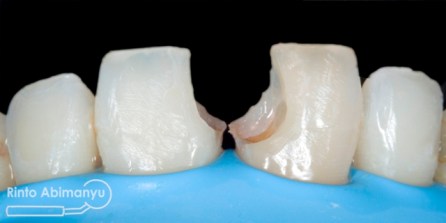

Ini kondisi gigi pada saat datang…

Kondisi awal gigi 11

Terlihat kondisi gigi 11 dan 21 yang ada tambalannya di mesial, ada karies sekunder dan bentuk tambalan tidak mengikuti anatomi gigi 11 dan 21 seharusnya…